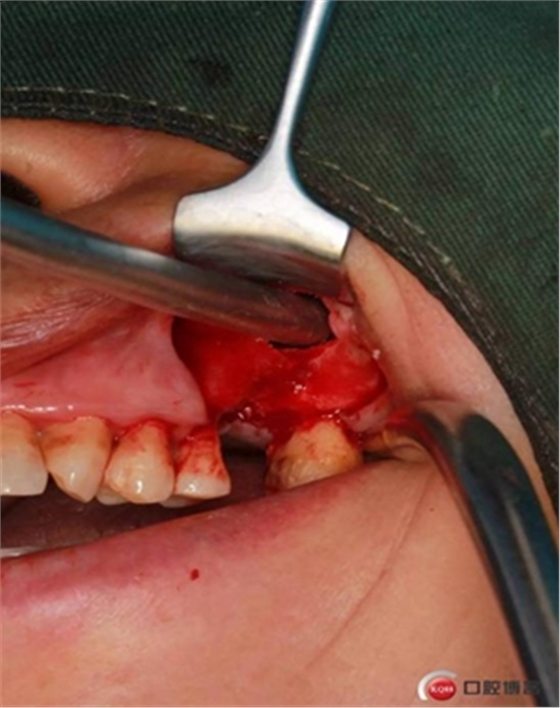

大家好,我是梁老師的助理小依。由于梁老師每天手術(shù)檔期安排較滿,加上經(jīng)常出差講課,沒有時間整理病例 。為了方便大家更及時的了解梁老師最新手術(shù)動態(tài),以后將由我為大家整理并推送梁老師最新經(jīng)典案例。案例文字旁白少,但圖片會盡量完整展示手術(shù)全過程,供大家學(xué)習(xí)參考。有任何問題,可以留言,梁老師會親自為大家解答。感謝大家對梁老師的支持和關(guān)注!